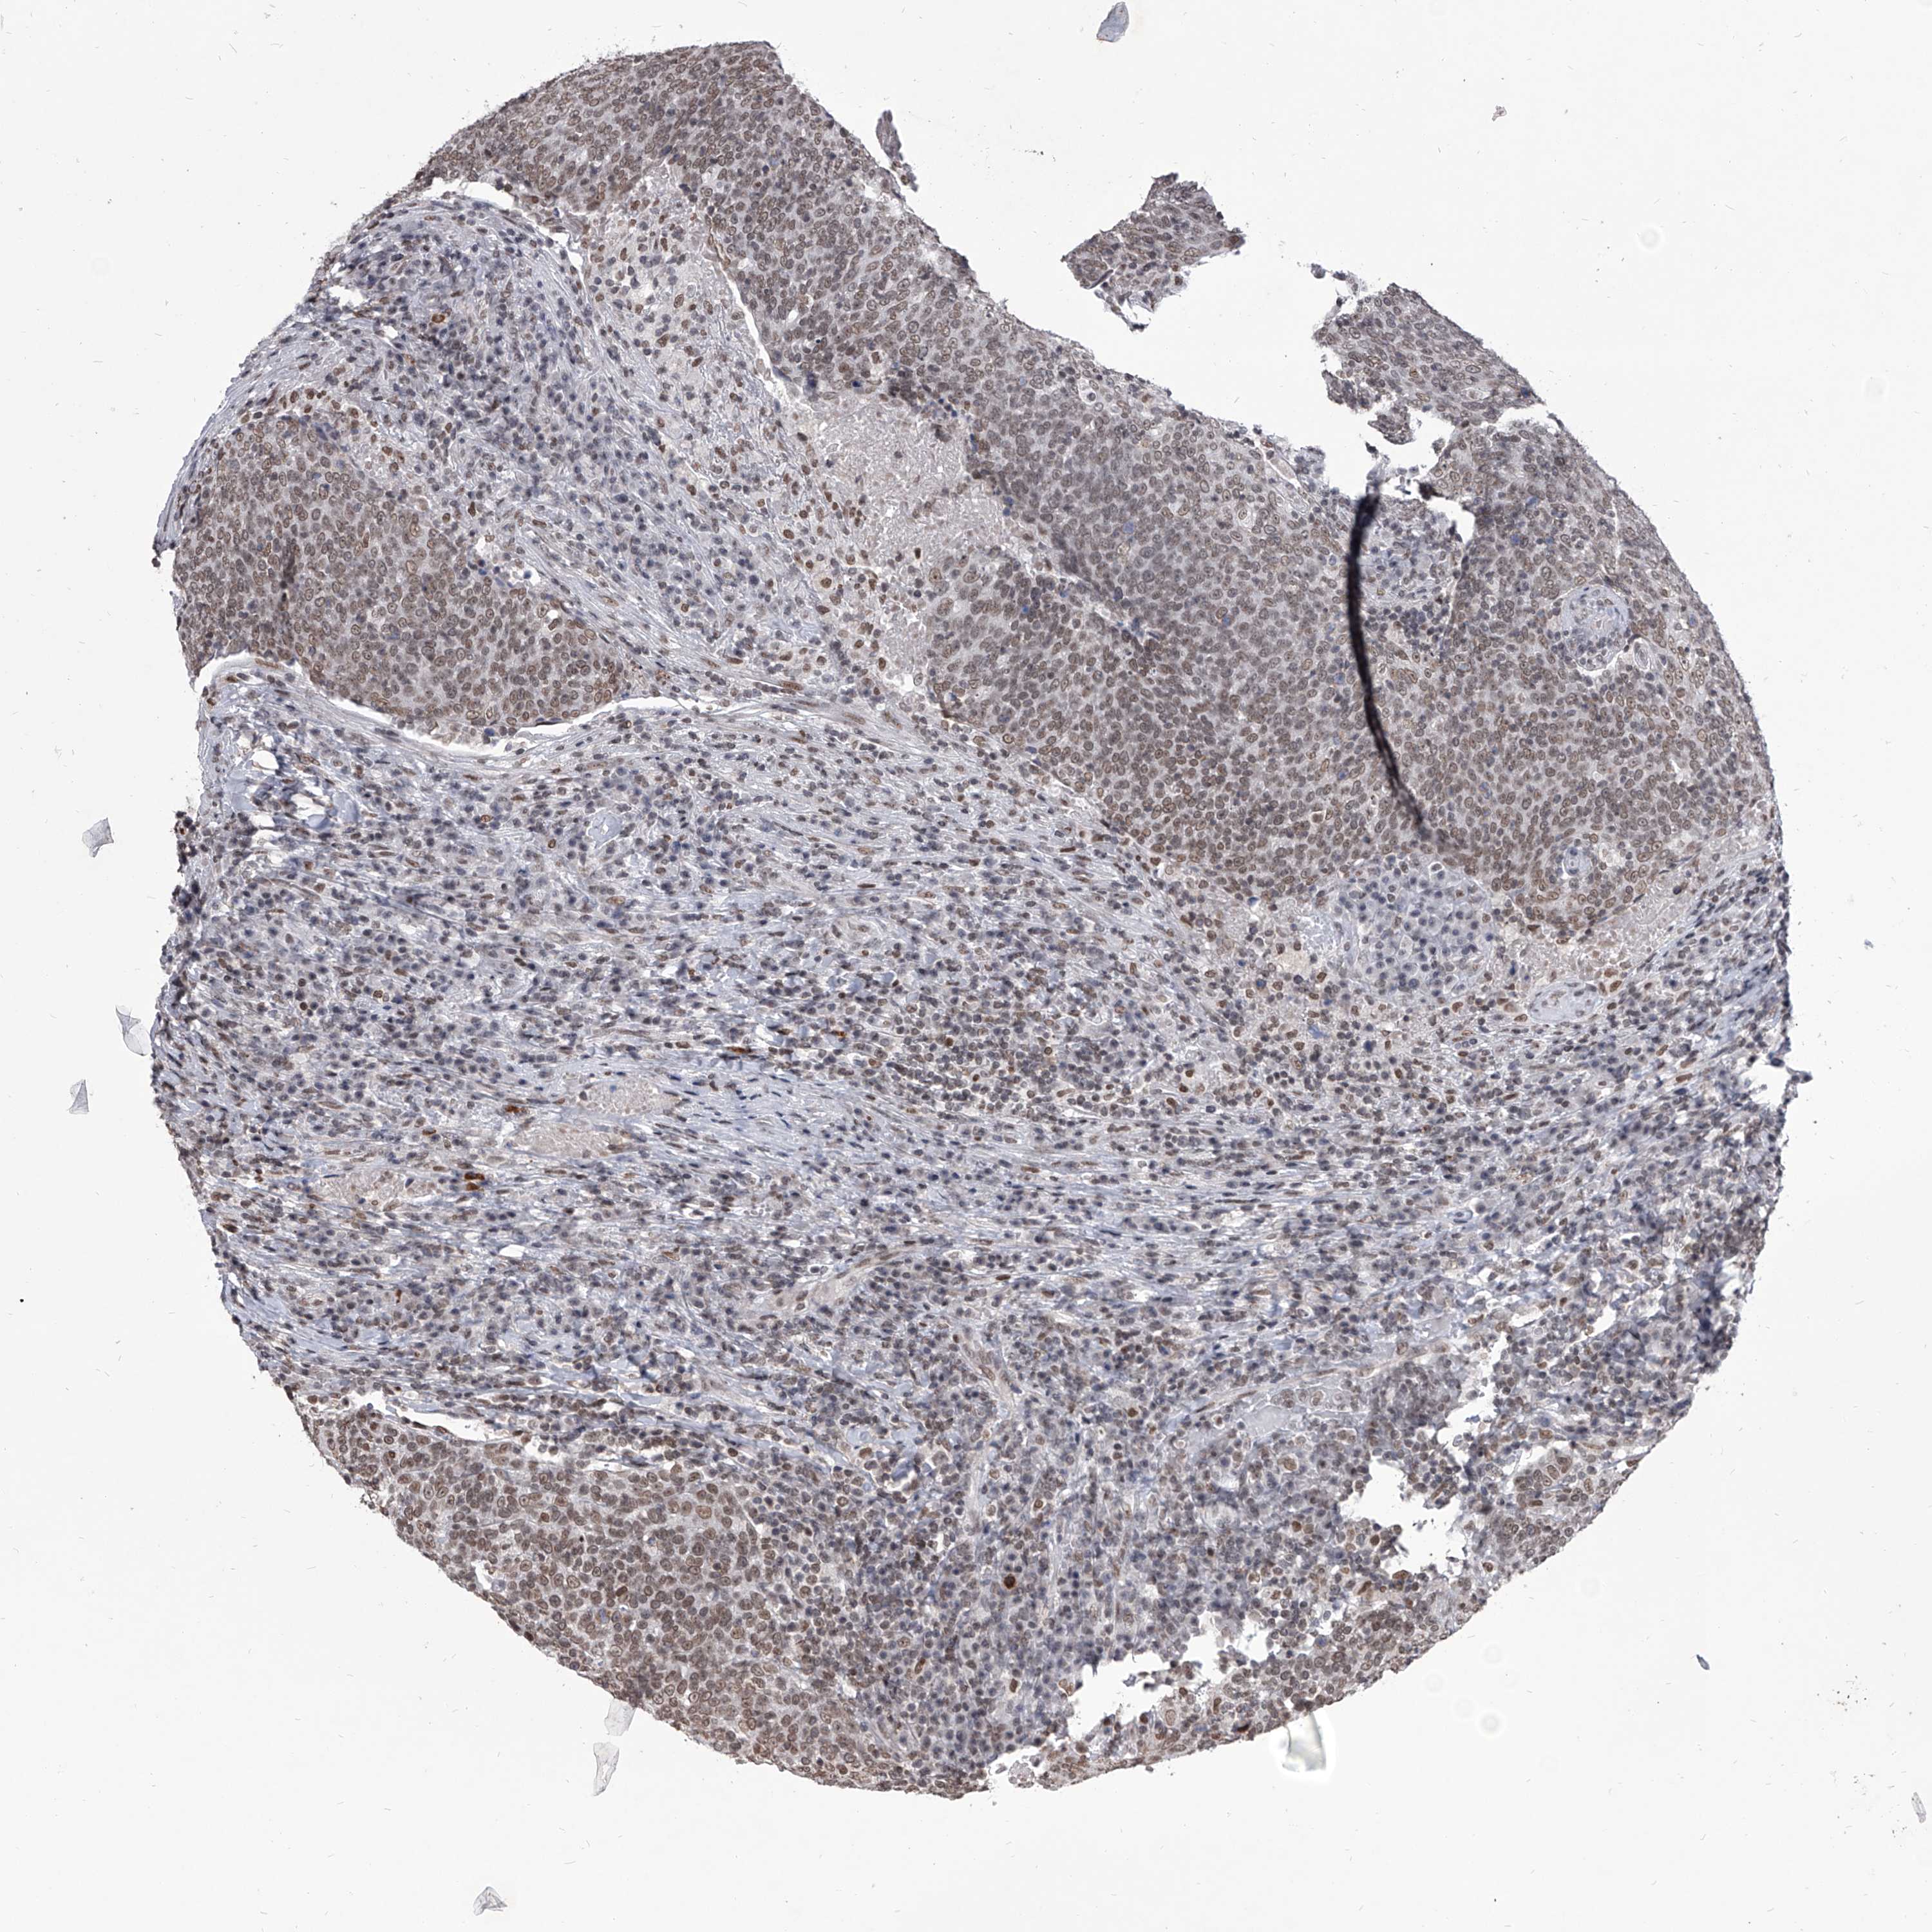

HEAD AND NECK CANCER - Protein expressioni

A mouse-over function shows sample information and annotation data. Click on an image to view it in a full screen mode. Samples can be filtered based on level of antibody staining by selecting one or several of the following categories: high, medium, low and not detected. The assay and annotation is described here.

Note that samples used for immunohistochemistry by the Human Protein Atlas do not correspond to samples in the TCGA dataset.

Antibody stainingi

Antibody staining in the annotated cell types in the current human tissue is reported as not detected, low, medium, or high, based on conventional immunohistochemistry profiling in selected tissues. This score is based on the combination of the staining intensity and fraction of stained cells.

Each image is clickable and will lead to virtual microscopy that enables deeper exploration of all samples and also displays staining intensity scores, fraction scores and subcellular localization as well as patient and tissue information for each sample.

Antibody HPA031600

Staining

High

Medium

Low

Not detected

Intensity

Strong

Moderate

Weak

Negative

Quantity

>75%

75%-25%

<25%

None

Location

Nuclear

Cytoplasmic/membranous

Cytoplasmic/membranous,nuclear

Squamous cell carcinoma, NOS

Squamous cell carcinoma, metastatic, NOS

Adenocarcinoma, NOS